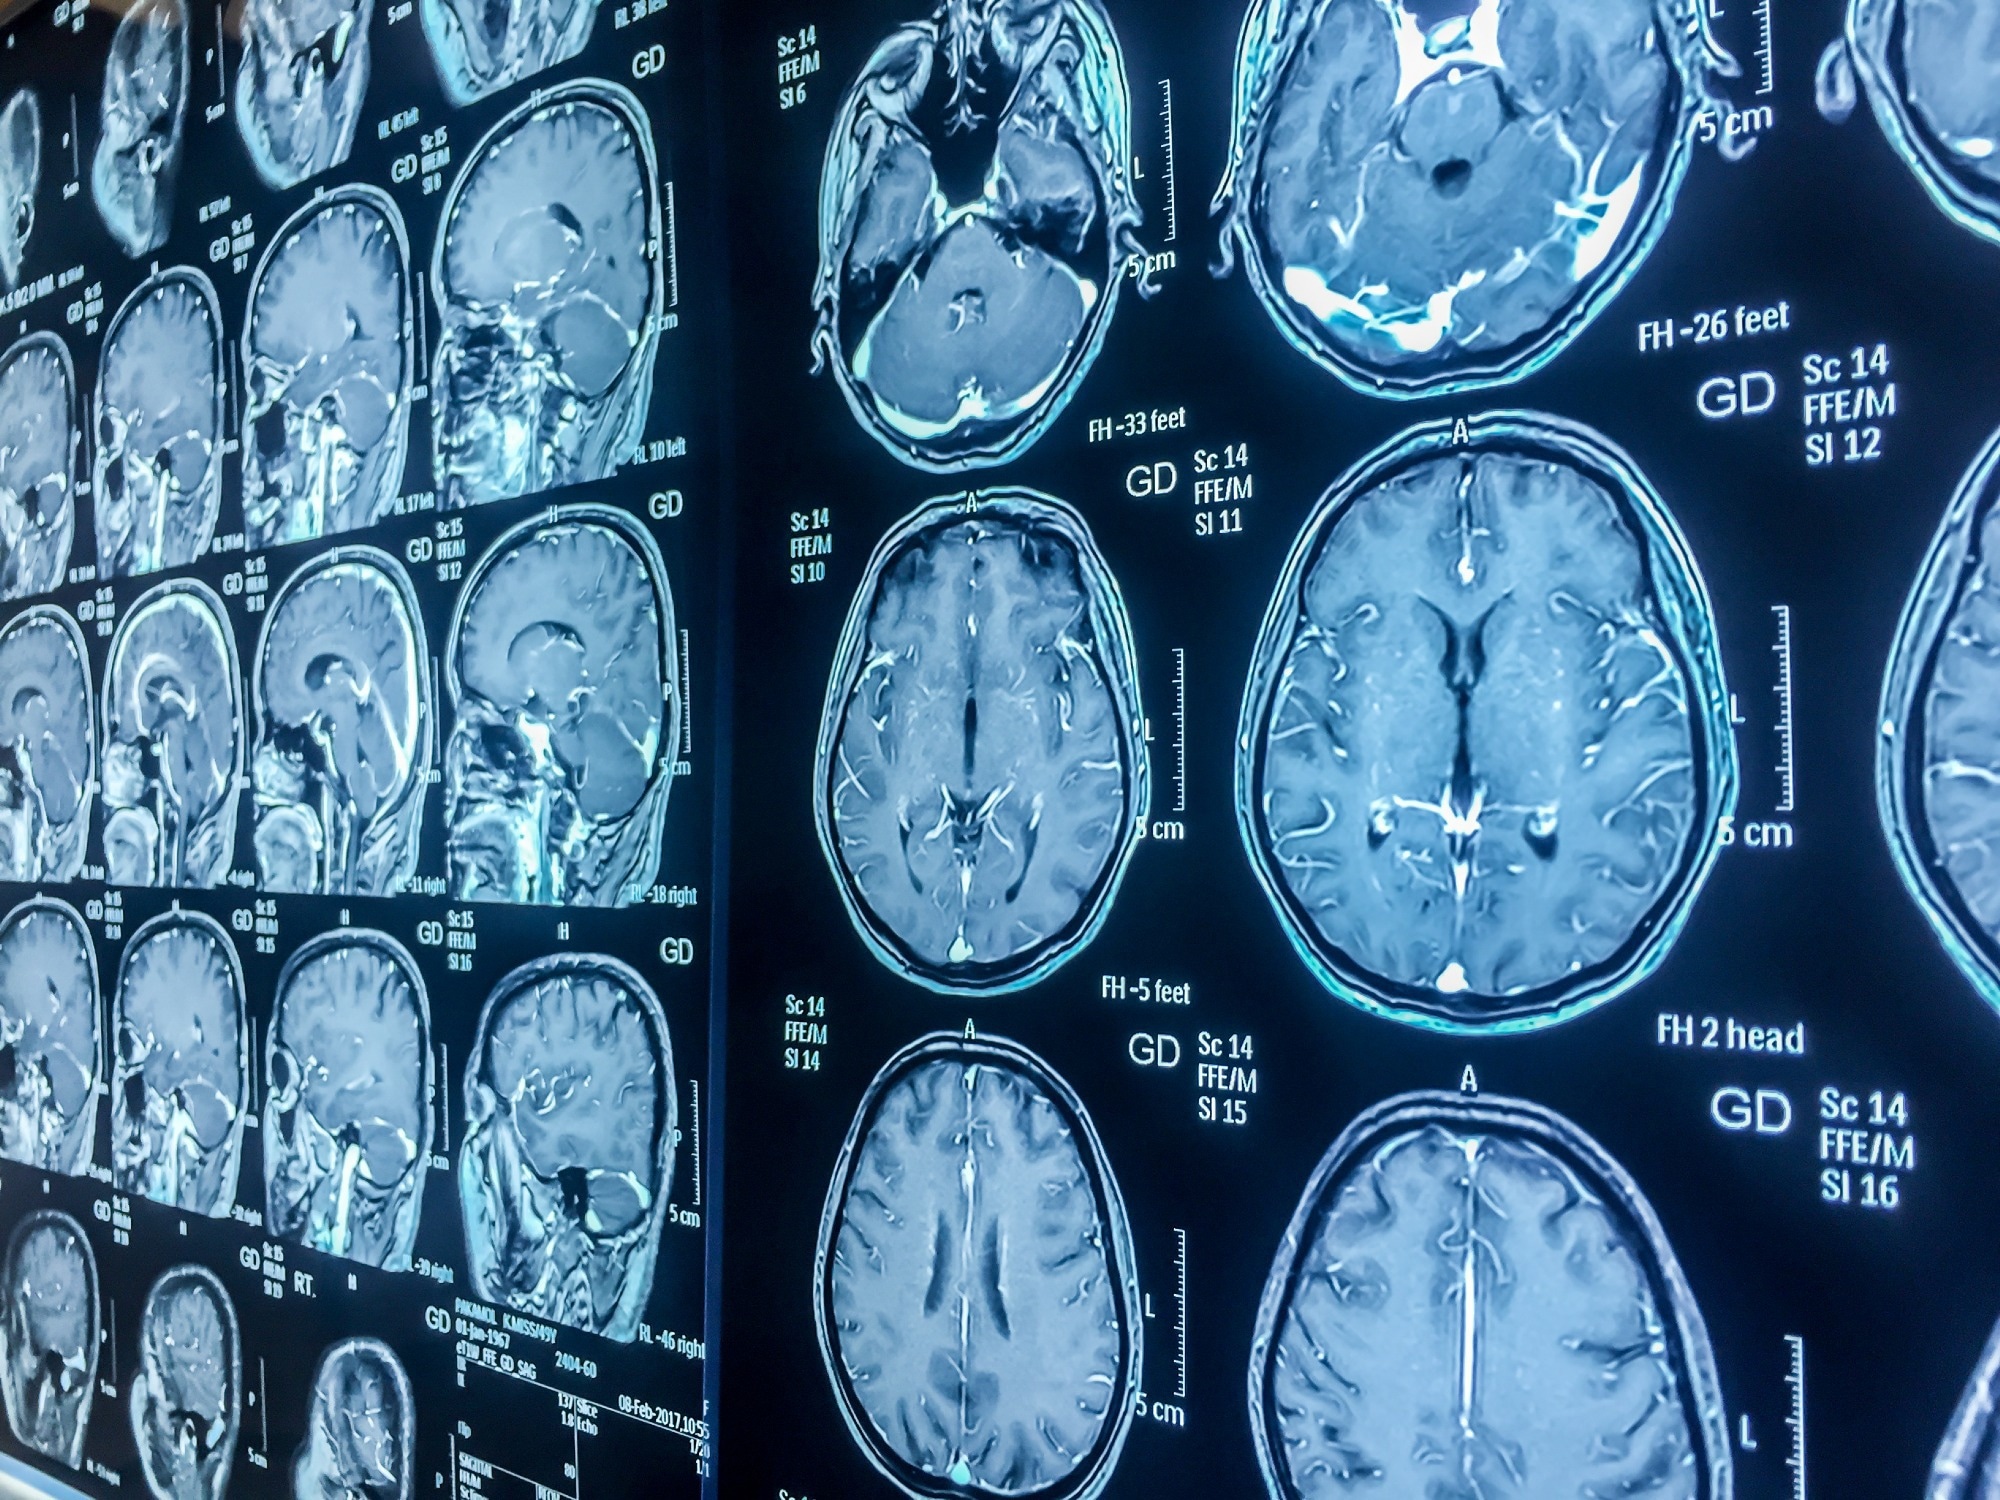

Study: Pediatric traumatic brain injury as a risk factor for psychosis and psychotic symptoms: a systematic review and meta-analysis. Image Credit: Karan Bunjean / Shutterstock.com